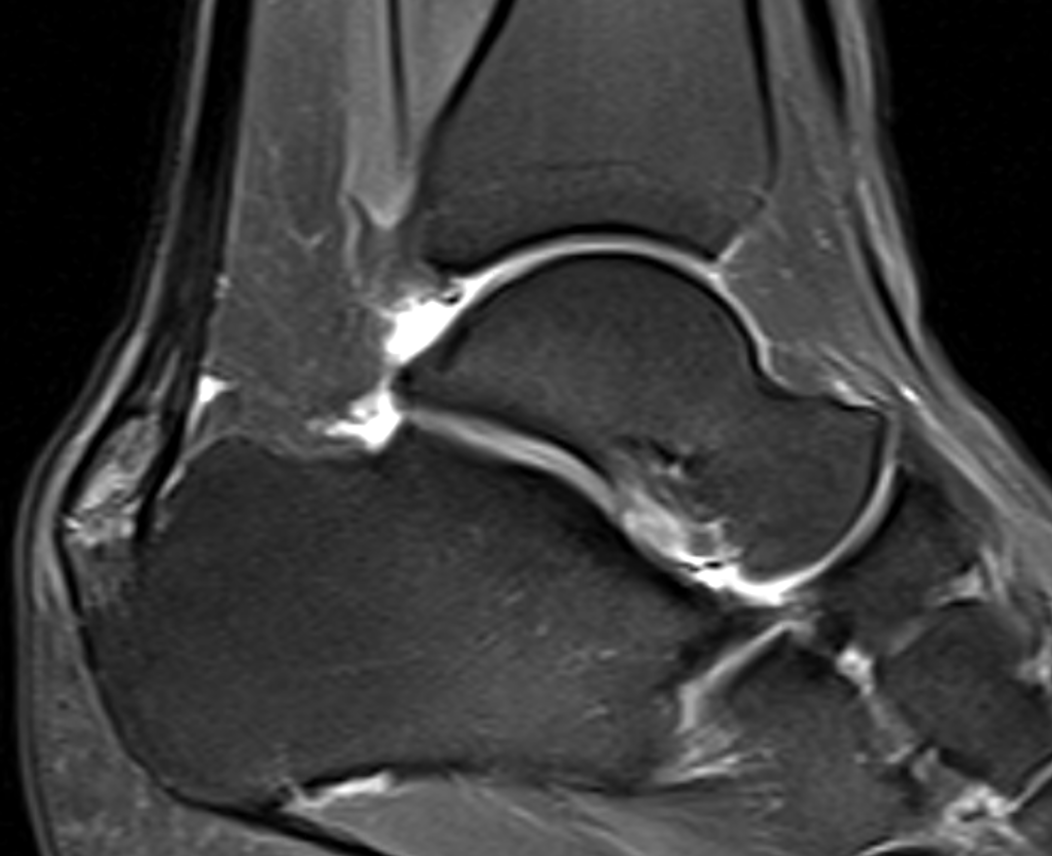

Surgery for non-insertional (mid-portion) Achilles tendinopathy

What problems is surgery addressing?

In mid-portion Achilles tendinopathy, surgery targets areas of degenerative tendon tissue, thickening, scarring, and poor tendon gliding that prevent normal healing.

Insertional Achilles tendinopathy involves pain where the tendon attaches to the heel bone and may include:

- Degenerative tendon tissue

- Bony prominence or heel spur

- Compression of the tendon against the heel bone